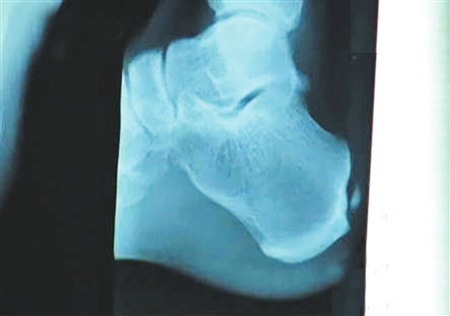

手術(shù)要取出的鈣化物就在這里。 圖片來源:華西都市報

北京時間12月6日凌晨,備受關(guān)注的中國飛人劉翔在休斯頓赫曼紀(jì)念醫(yī)院的跟腱手術(shù)成功結(jié)束。